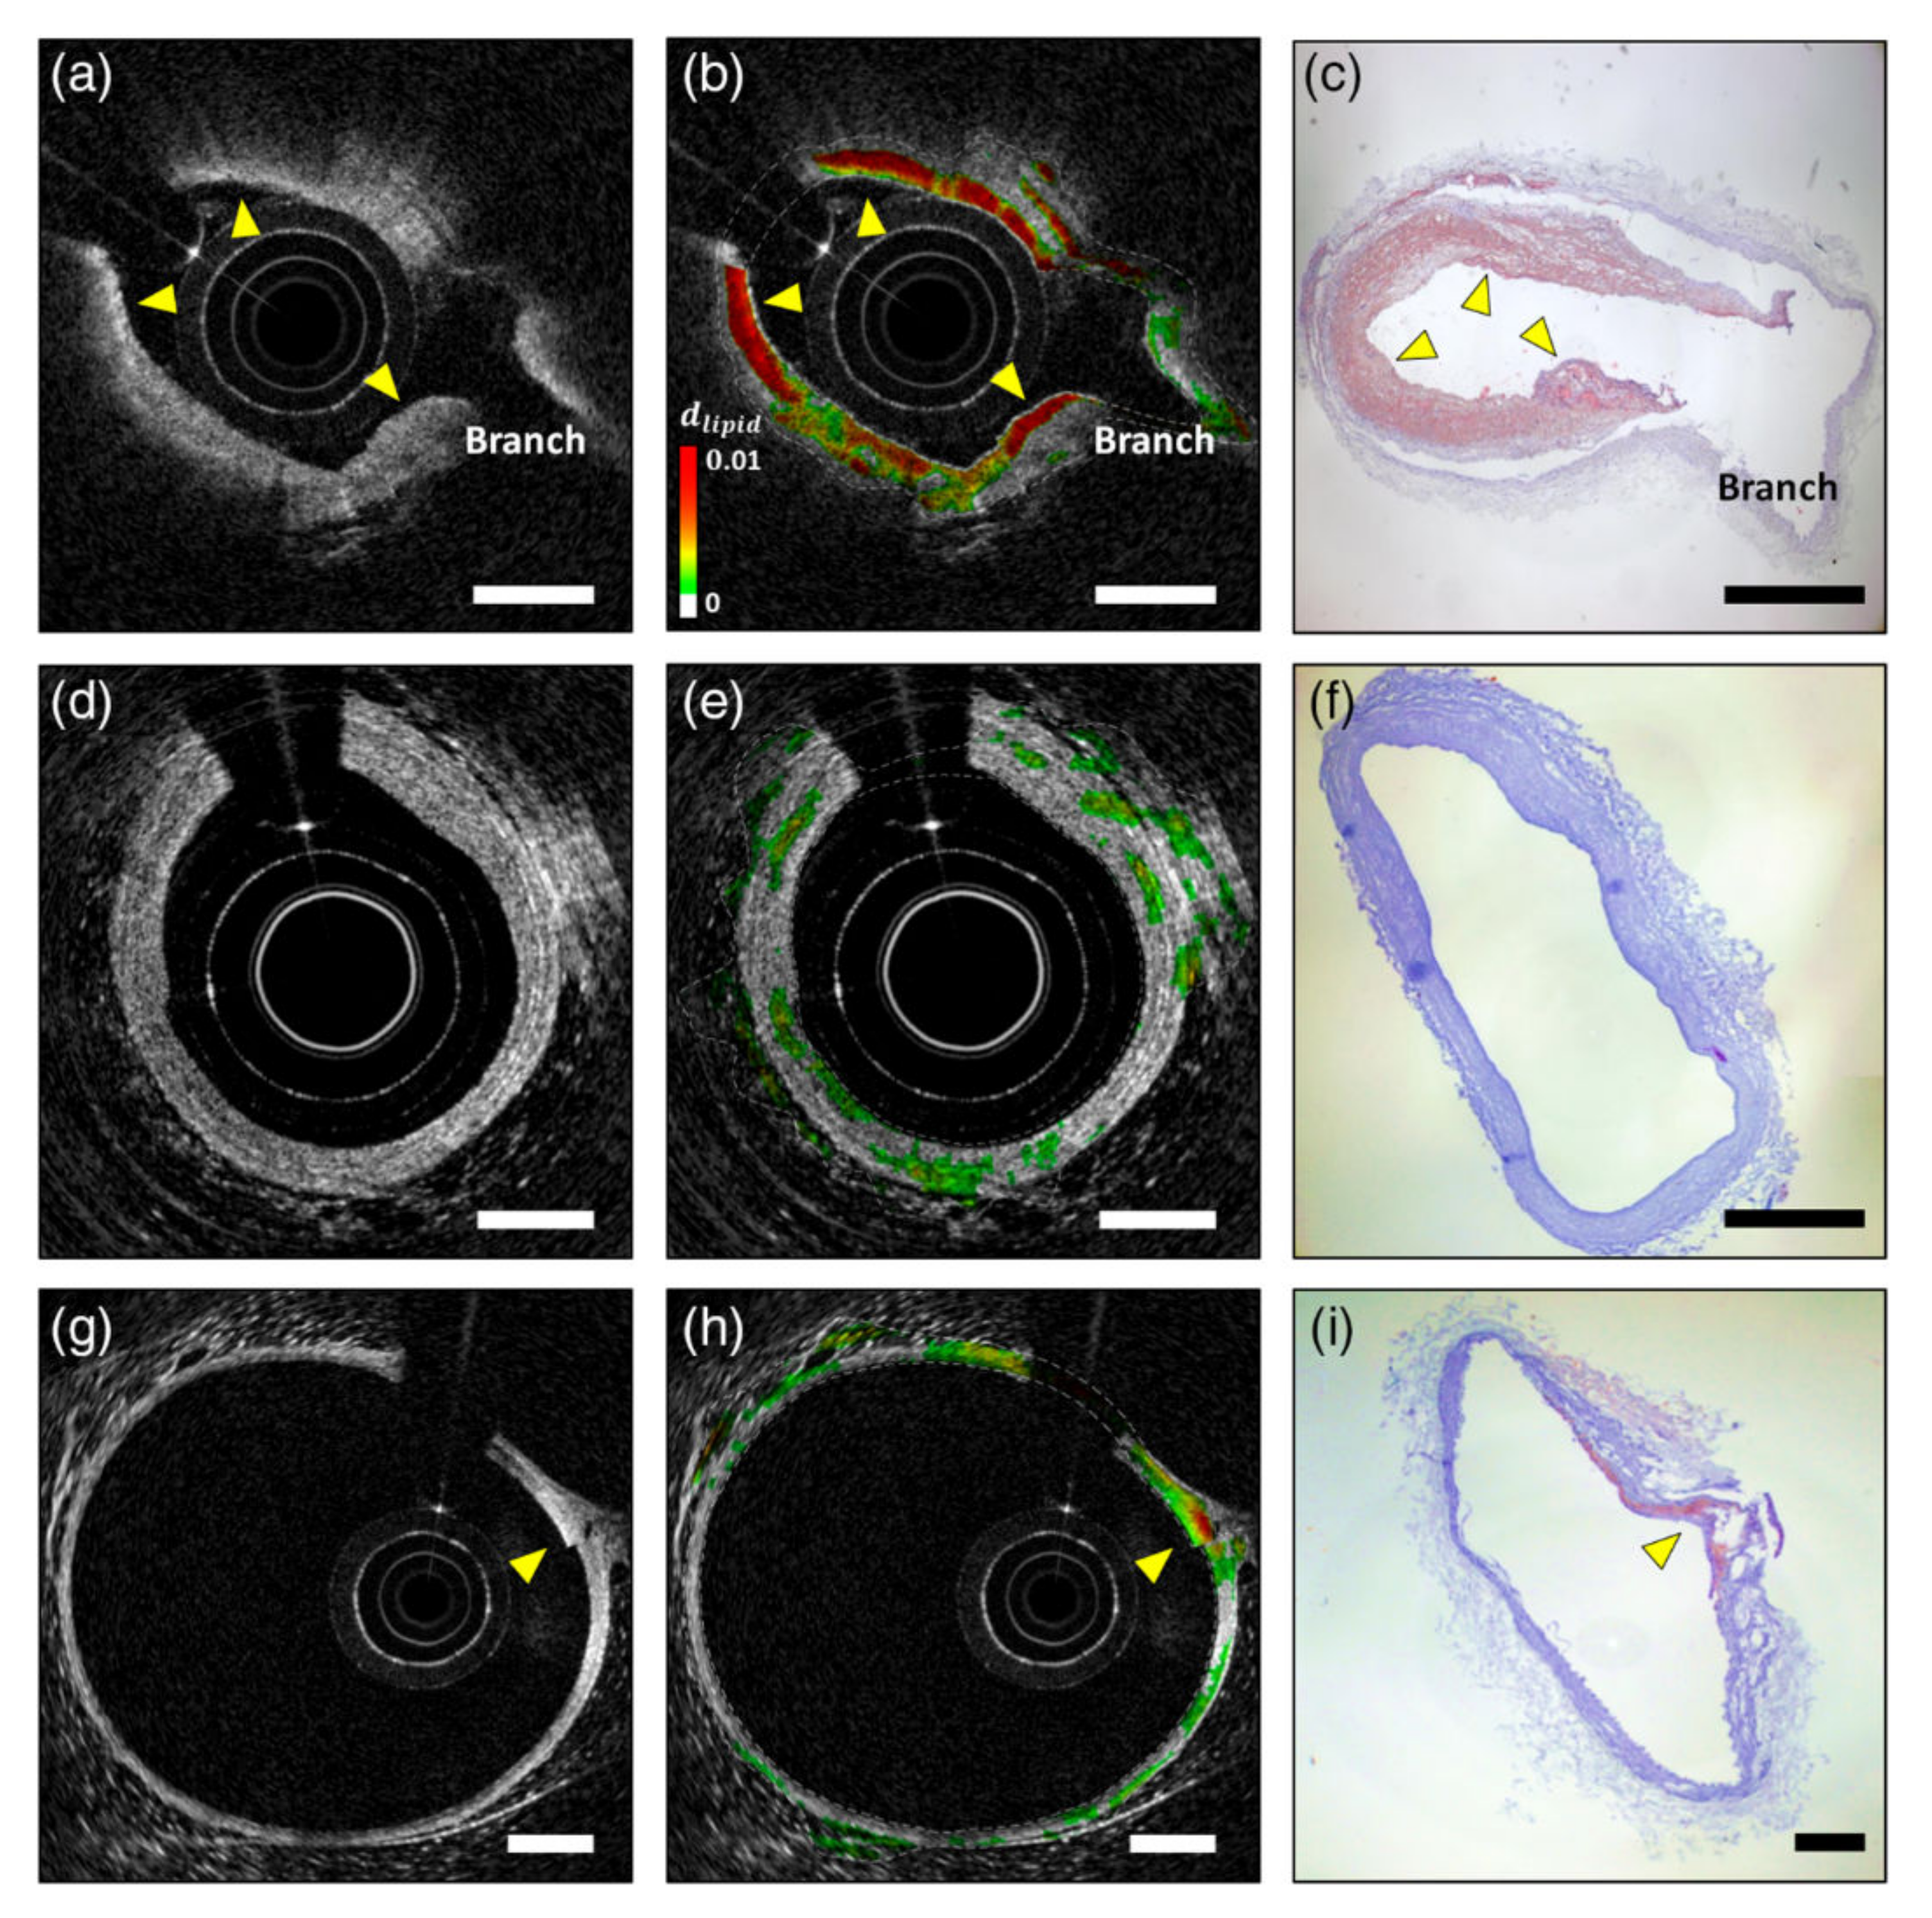

Hemoglobin is the major endogenous contrast agent for S-OCT, while NIR dyes and nanoparticles are two main categories of exogenous S-OCT contrast agents. Morgner et al., developed the first S-OCT device with probe light bandwidth of 230 nm and center wavelength at 800 nm [119]. Its depth and lateral resolution are about 1 µm and 5 µm, respectively. This S-OCT system detected the whole bandwidth of the available spectrum in one measurement and enhanced the image contrast of a Xenopus laevis tadpole without any exogenous contrast agents during the demonstration. Xu et al., gave an exhaustive discussion about the common NIR dyes suitable for S-OCT scan and demonstrated that NIR dyes can work along well with other nanoparticles as contrast agents. For example, NIR dyes mixed with 100 nm nanospheres [120]. NIR dyes can also be encapsulated in protein nanospheres as OCT contrast agents [18]. Most of the S-OCT are software-based, but Yang et al., developed a novel S-OCT hardware to detect molecules by triangulating a peak in the absorption spectra with three different light sources [121]. They used this device to map the distribution of indocyanine green in Xenopus laevis. Xu et al., also pointed out that plasmon resonant nanoparticle contrast agents with high extinction coefficients could be detected using S-OCT. In general, particles larger than 100 nm are dominated by resonant scattering effects, whereas particles smaller than 100 nm exhibit absorption. Oldenburg et al., presented a type of gold nanorods as a contrast agent, which is 50 nm long with an aspect ratio of 3 [122,123]. Its plasmon-resonance peak is 755 nm and overlaps the OCT light wavelength band. The contrast agents enable S-OCT to achieve clear images with low noise in excised human breast carcinoma. Xingde Li et al., presented a series of research on the gold nanocages as contrast agents of S-OCT [124,125]. Gold nanocages with an edge length of 35 nm were produced, which have a tunable plasmon resonance peak in the NIR region. Experiments showed that gold nanocages have five orders of magnitude larger absorption ability than common dyes in tissue phantoms. On that basis, the first gold nanocage-based scattering-dominant agent was synthesized and validated for in vivo tumor imaging, proving significant contrast enhancement. Spicer et al., calibrate the system spectral response of an S-OCT system with a solution of 80 nm polystyrene beads in water [126]. Si et al., also used PEGylated gold nanobipyramids as contrast agents for multiplexing in a tumor-implanted mouse model. In vivo imaging of mouse pinnae showed that the spectral contrast in the tissue increases linearly for nanoparticle concentration [127]. Nam et al., reported an algorithm to characterize lipid plaques with S-OCT based on a Gaussian center of mass (GCOM) metric [128]. Using an atherosclerotic rabbit model, they demonstrated the in vivo S-OCT images of lipid-rich plaques as Figure 10 shows. The plaques detected using S-OCT match well with ORO-stained histological sections, and the validation results indicate that this method has a sensitivity and specificity of 94.3% and 76.7% for lipid detection, respectively.